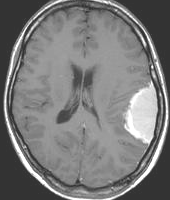

手術後のMRIです。腫瘍は全部取れていて後遺症もありません。圧迫されて変形していた脳はきれいに元に戻っていますし脳浮腫も消えました。一般的に若い人の脳ほどきれいに元に戻ります。注意しなければならないのは,少しでも取り残した場合には,何年か後に10%-20%くらいで再発があることです。もちろん完全に取れた時の再発はほとんどありません。